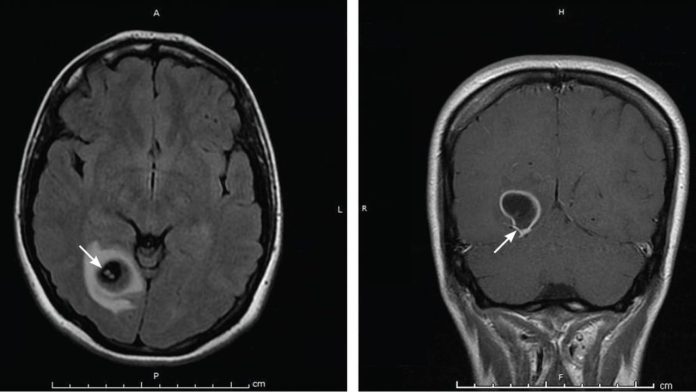

Neurocysticercosis infections are more common in areas with poor sanitation and hygiene, and larvae may enter the brain, spinal cord, or other neurological tissues through contaminated water consumption. The pig tapeworm (Taenia solium) larvae cause neurocysticercosis, an avoidable parasitic infection that affects the central nervous system. The larvae create cysticercosis, a disorder that occurs when the larvae damage different regions of the body.

A type of brain infection called neurocysticercosis is brought on by parasites. It is brought on by Taenia solium larval cysts, often known as pig tapeworms. Eating undercooked meat and contaminated vegetables, especially root vegetables that grow underground, is the major way that it is spread. Taenia solium larval cysts puncture the human gut after ingestion, resulting in neurocysticercosis. The disease known as neurocysticercosis is brought on by tiny worms that live in unclean and unsanitary environments. It is primarily a byproduct of undercooked pork. Thus, the risk of contracting this disease, which directly damages the brain and spinal cord, is increased in individuals who eat pork that has been incorrectly cooked.